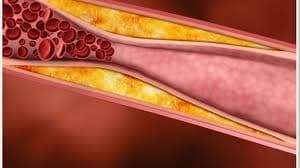

Antes de mais nada, o Tratamento para Doença Arterial Coronária reduz riscos cardíacos ao controlar placas nas artérias e melhorar a circulação do sangue no coração.Além […]

Antes de mais nada, o Tratamento para Dislipidemia controla colesterol alto, triglicerídeos elevados e outros distúrbios lipídicos que aumentam o risco cardiovascular.Além disso, acompanhamento médico contínuo […]

Antes de mais nada, Infarto do Miocárdio ocorre quando o fluxo de sangue para o coração diminui ou bloqueia totalmente, causando lesão no músculo cardíaco.Além disso, […]

Antes de mais nada, Dislipidemia representa um desequilíbrio nos níveis de colesterol e triglicerídeos que compromete diretamente a saúde do coração.Além disso, essa alteração metabólica aumenta […]

Antes de mais nada, Doença Arterial Coronária representa uma das principais causas de infarto e morte cardiovascular no Brasil, exigindo diagnóstico rápido e acompanhamento especializado.Além disso, […]